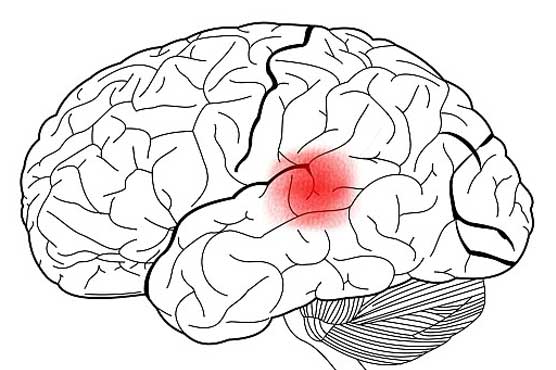

Summary Study revealed that brain speech processing centre is at a different place than originally believed.

The part of the brain used for speech processing is in a different location than originally believed, according to a US study Monday that researchers said will require a rewrite of medical texts.Wernickes area, named after the German neurologist who proposed it in the late 1800s, was long believed to be at the back of the brains cerebral cortex, behind the auditory cortex which receives sounds.But a review by scientists at Georgetown University Medical Center of more than 100 imaging studies has shown it is actually three centimeters closer to the front of the brain, and is in front of the auditory cortex, not behind.Textbooks will now have to be rewritten, said neuroscience professor Josef Rauschecker, lead author of the study which appears in the Proceedings of the National Academy of Sciences.We gave old theories that have long hung a knockout punch.Rauschecker and colleagues based their research on 115 previous peer-reviewed studies that investigated speech perception and used brain imaging scans -- either MRI (functional magnetic resonance imaging) or PET (positron emission tomography).An analysis of the brain imaging coordinates in those studies pointed to the new location for Wernickes area, offering new insight for patients suffering from brain damage or stroke.If a patient cant speak, or understand speech, we now have a good clue as to where damage has occurred, said Rauschecker.It also adds an intriguing wrinkle to the origins of language in humans and primates, who have also been shown to process audible speech in the same region of the brain.This finding suggests the architecture and processing between the two species is more similar than many people thought.Lead author Iain DeWitt, a PhD candidate in Georgetowns Interdisciplinary Program in Neuroscience, said the study confirms what others have found since brain imaging began in earnest in the 1990s, though some debate has persisted.The majority of imagers, however, were reluctant to overturn a century of prior understanding on account of what was then a relatively new methodology, he said.The point of our paper is to force a reconciliation between the data and theory.